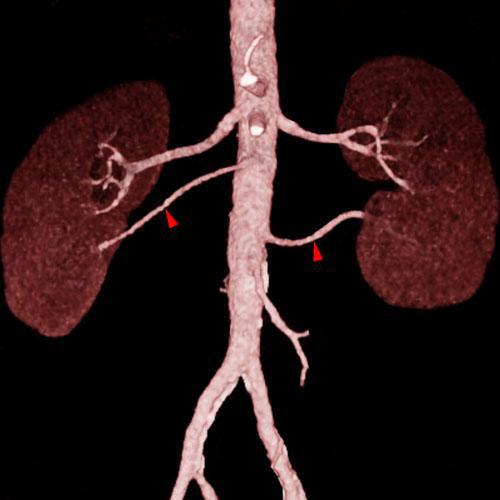

Arteria renal torácica